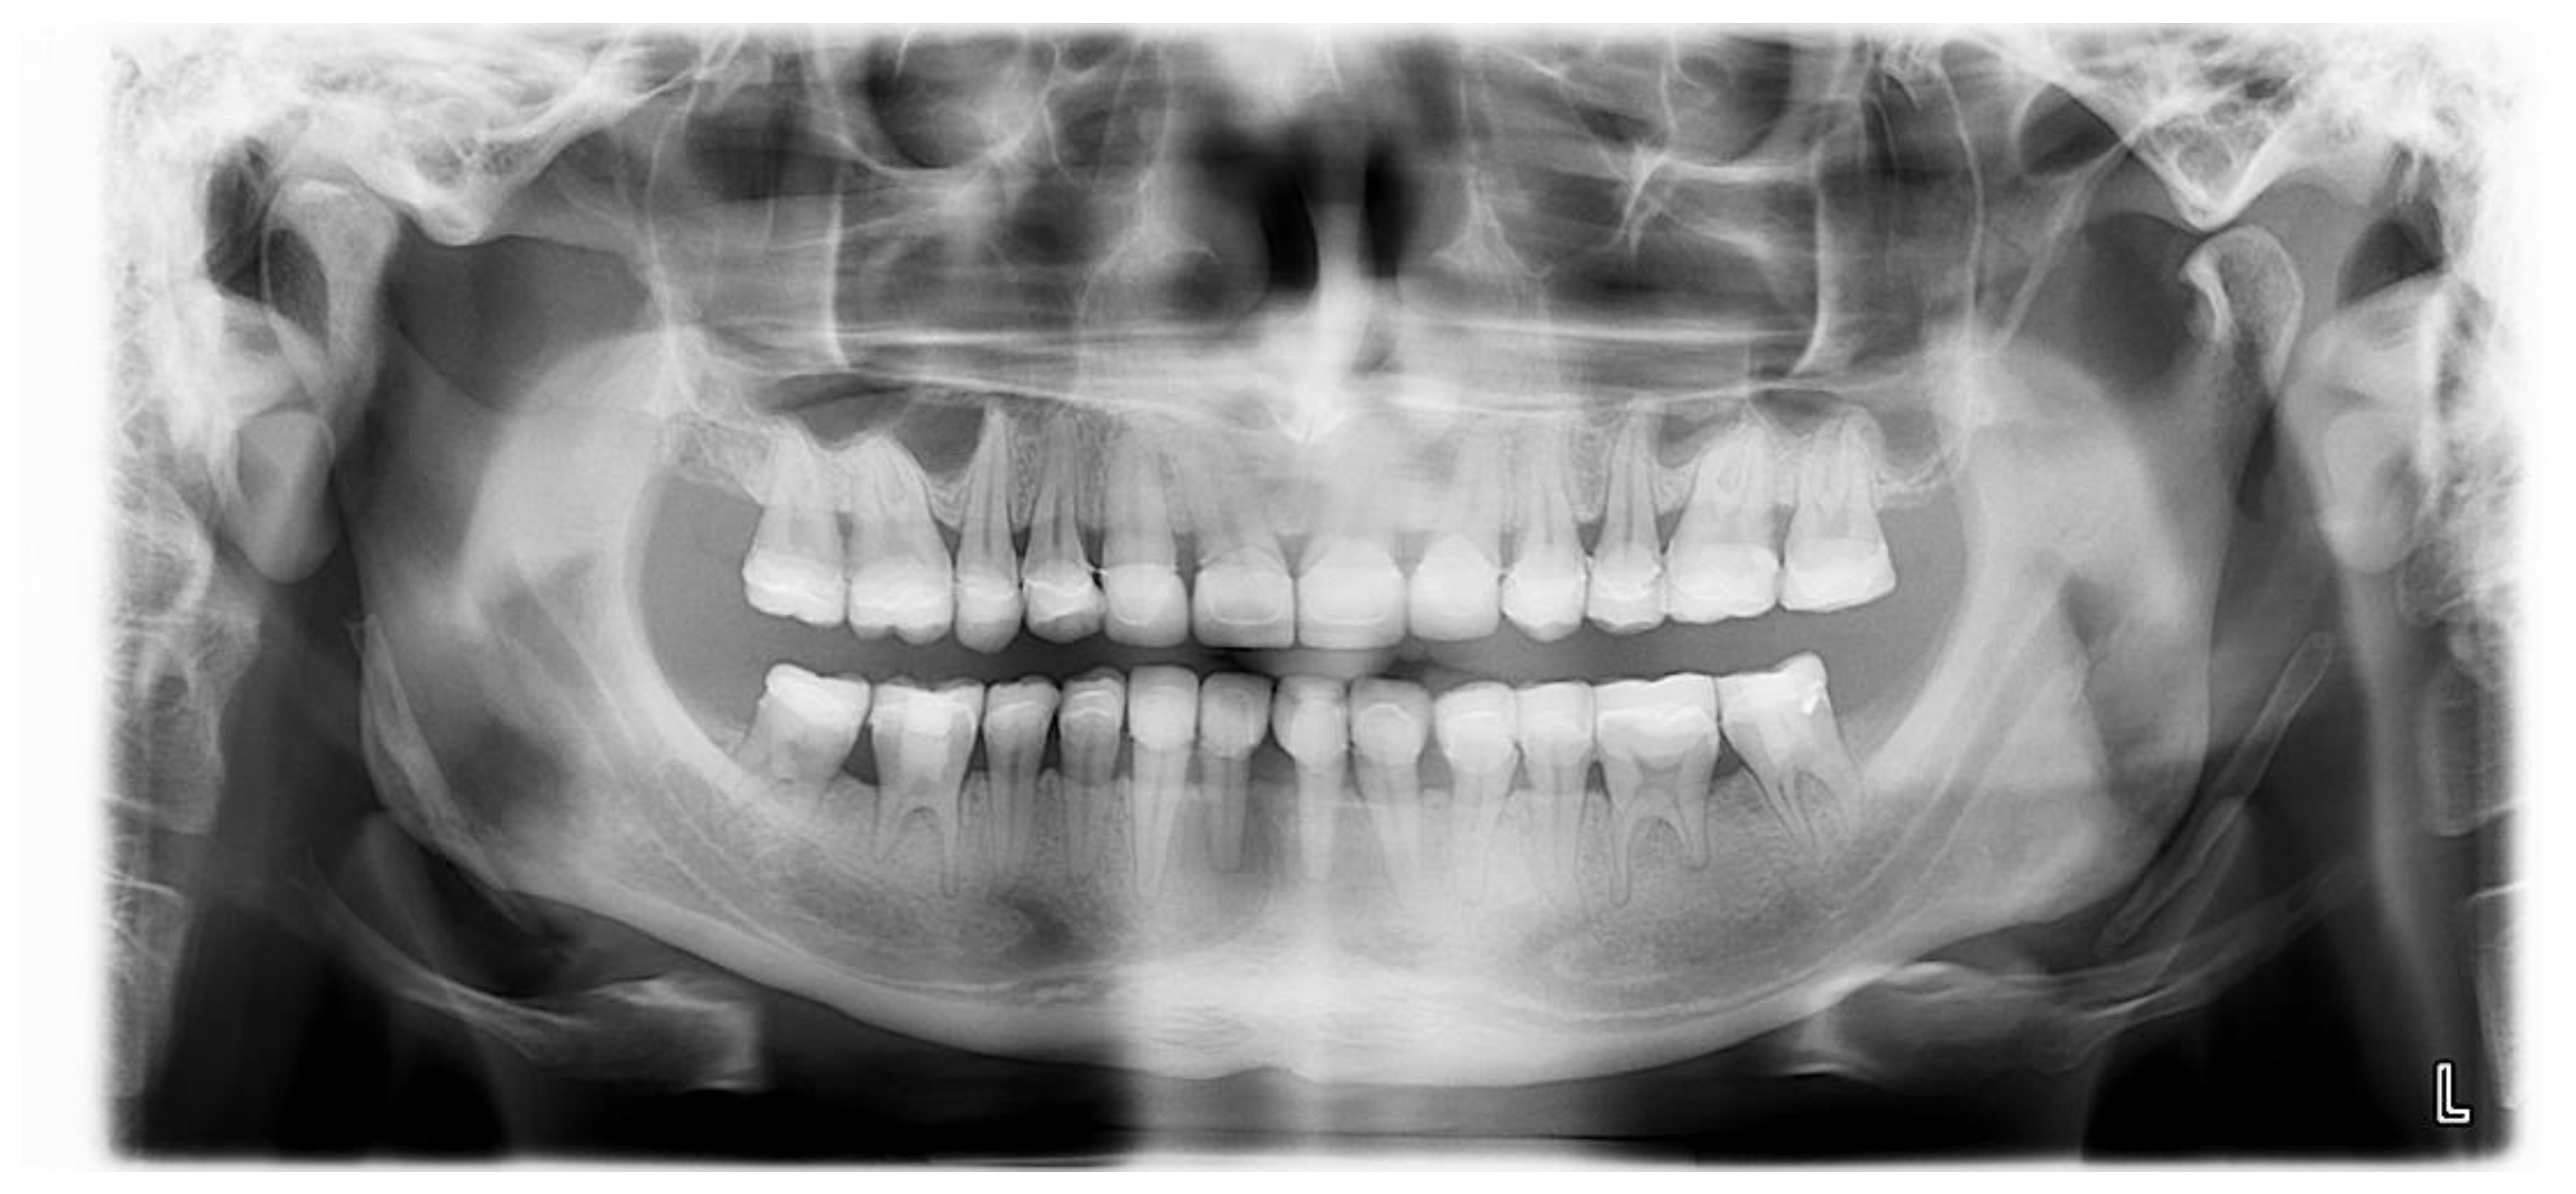

The GOHAI was performed at 8 months after the end of treatment, and the score obtained was 59/60, indicating an excellent oral quality of life. An orthopantomogram of the patient at 8 months after the end of the dental treatment is presented in Figure 16.

Figure 16.

Orthopantomogram of the patient at 8 months after the end of the dental treatment.